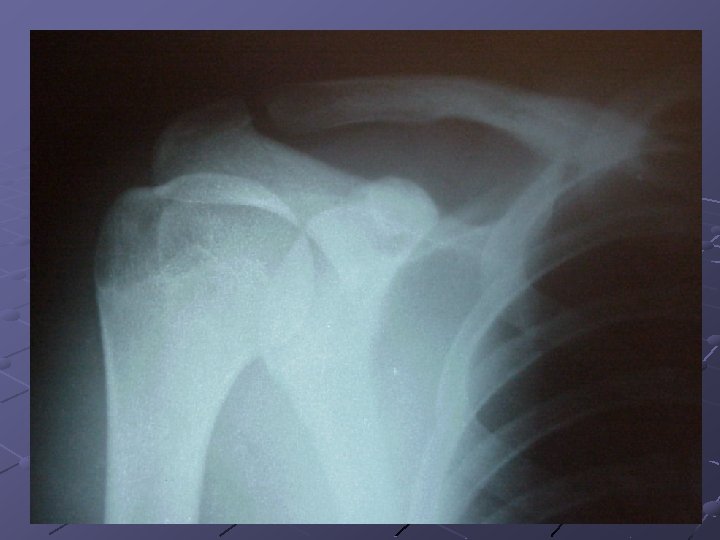

Case #2 24 -year-old male handball player Fell onto his shoulder after being pushed Intense pain Hand is tingling and arm feels like it’s hanging X-rays

X RAYS DIAGNOSIS? ? ?

Shoulder Dislocation/Anterior Instability Humeral head dislocates from glenoid fossa Almost always anterior (95%) Usually traumatic with injury to capsulelabrum complex